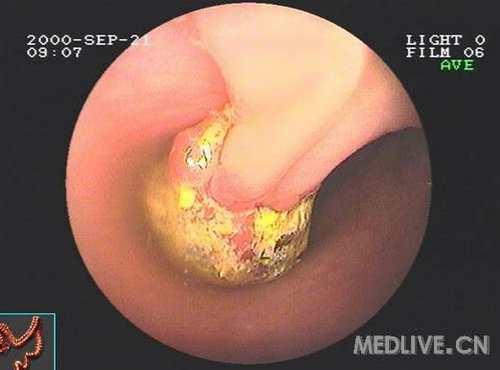

胃肠道结核

胃肠道结核一般是结核病多系统累及的一部分,在没有有效的抗结核治疗的年代,70%的进展期肺结核患者伴有胃肠道结核。目前,胃肠道结核只占结核病的1%。

内镜下,多累及回盲部,可见充血、水肿、溃疡、肿物等表现,需与克罗恩病和结肠癌相鉴别,确诊依赖活检病理发现抗酸杆菌。